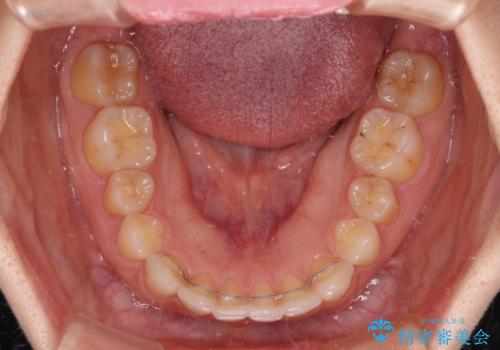

ギリギリとなりましたが、結婚式直前にワイヤー装置を外すことができました。

ワイヤー装置除去後に細かい部分を短期間のマウスピース矯正にて仕上げました。